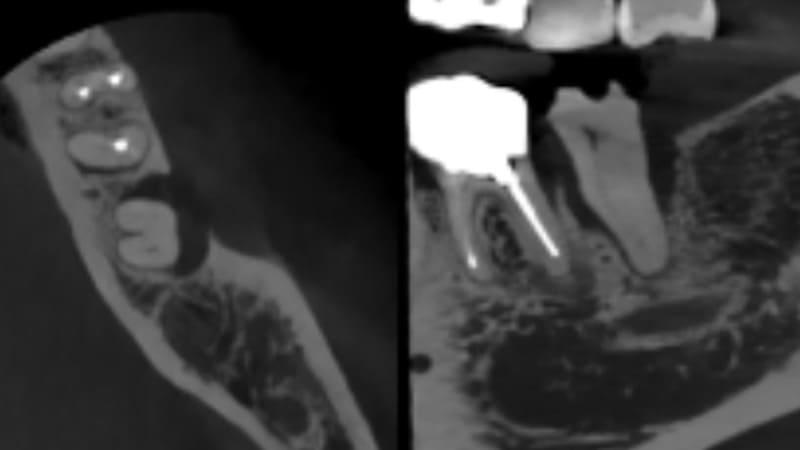

症例②:左上がずっと違和感がある

| 治療科目 | 歯周組織再生療法(エムドゲイン使用) |

|---|---|

| 主訴 | 左上がずっと違和感がある |

| 治療期間 | 半年 |

| 治療費 | 220,000円 |

| 治療内容 | エムドゲインとバイオスを使い再生療法を行った。 |

| 治療のリスク | 角化歯肉の状態により再度感染を起こす可能性があり、遊離歯肉移植の併用が必要なこともあります。 清掃方法によって再感染する可能性があり、定期的な通院でチェックしていく必要があります。 |